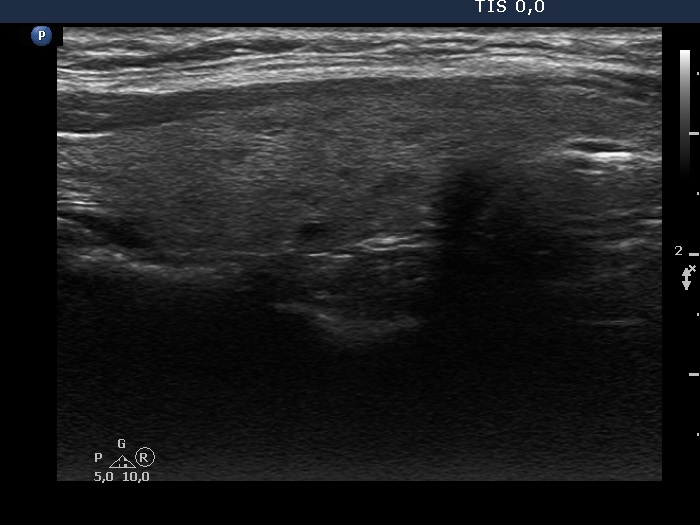

Ultrasonography. The thyroid was echonormal and had tiny, moderately hypoechoic areas. The echogenicity index was around 10%. There was a dominantly hypoechoic, heterogeneous nodule in the left lobe. The lesion presented various echogenic figures, including microcalcifications and amorphous hyperechoic patches.